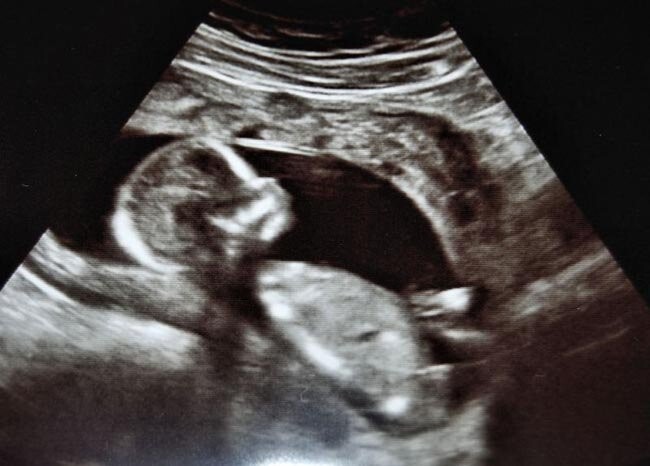

Más allá de la curiosidad por el sexo del bebé, el seguimiento médico es el pilar fundamental para garantizar un embarazo saludable. Las revisiones periódicas, las ecografías y los controles médicos permiten evaluar el desarrollo del feto y detectar posibles complicaciones a tiempo. Aunque muchas personas recurren a una calculadora para saber si es niño o niña por diversión, es importante no confundir estas predicciones con diagnósticos reales. La información médica fiable proviene exclusivamente de profesionales de la salud y de pruebas clínicas adecuadas.